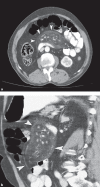

Subjects and methods: This retrospective study was carried out among patients with MP based on computed tomography (CT) scans from January 2012 to December 2015. The CT images were reanalyzed by study radiologists to confirm the previous MP diagnosis. Patients were divided into 2 groups, i.e., idiopathic and secondary, based on the presence or absence of associated predisposing factors such as trauma, malignancy, autoimmune disorders, ischemia, or previous abdominal surgery. The clinical characteristics of the 2 groups, as well as treatments, were assessed.

Results: Among the 19,869 CT scans, 36 patients (0.18%) with MP were identified (i.e., 19 [53%] females and 17 [47%] males). The median age was 54 years (range 26 - 76). Twenty-four patients (67%) were categorized into the idiopathic group. Malignancy was the predisposing factor in 8 (22%) of those patients. Furthermore, abdominal pain was the cardinal symptom observed in 22 patients (92%) in the idiopathic group. In the idiopathic group, 15 patients (63%) were treated with antibiotics and 16 (67%) were treated with nonsteroidal anti-inflammatory drugs (NSAID). One unresponsive patient was treated with colchicine. Symptomatic relief was achieved in all of the treated patients.